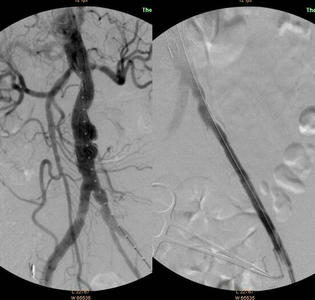

图左:示腹主动脉覆膜支架置入

图右:示左髂动脉覆膜支架置入